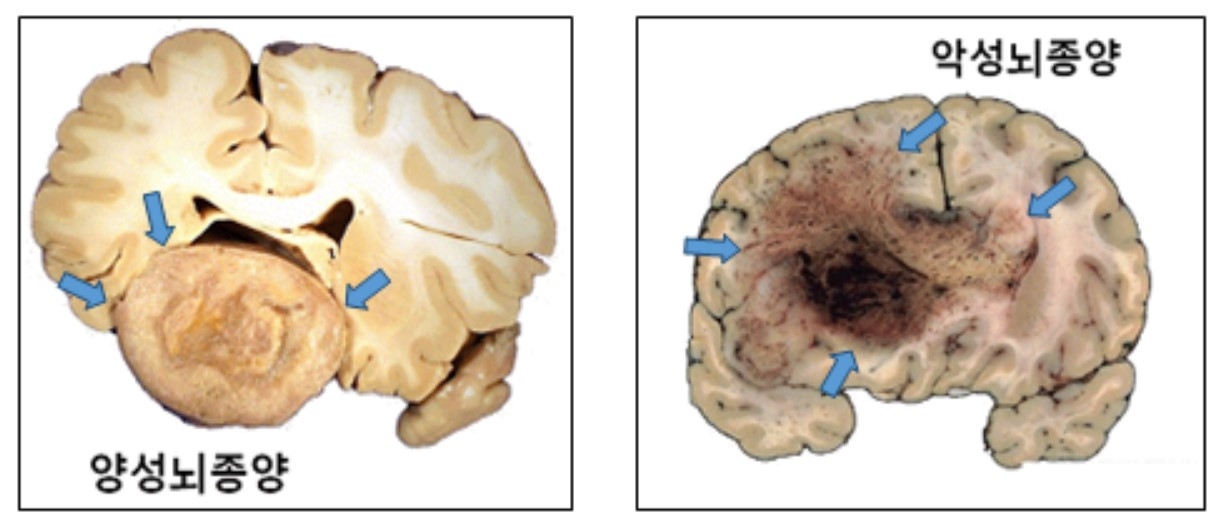

▶뇌토토사이트 케이 벳의 종류는?=뇌토토사이트 케이 벳은 조직학적 특성에 따라 양성과 악성으로 나눈다. 양성 뇌토토사이트 케이 벳은 성장속도가 1년에 1~2㎜ 미만으로 느리다. 주변 부위와 비교적 명확히 구분되기 때문에 수술을 통한 완치 가능성도 높다. 토토사이트 케이 벳의 크기나 위치에 따라 일상생활이 불편할 수 있어도, 5년 생존율이 90% 이상일 만큼 생명에 거의 지장이 없다. 따라서 별다른 증상이 없는 경우 경과관찰만 하며, 증상이 있거나 주기적으로 MRI를 촬영하며 관찰하다가 성장 속도가 일반적인 경우보다 빠르다고 판단 될 때 치료를 고려해도 늦지 않다. 대표적인 양성 뇌토토사이트 케이 벳에는 뇌를 둘러싼 수막(뇌막)에서 발생한 뇌수막종, 뇌의 정중앙부 하단에 위치한 ‘뇌하수체’에서 발생한 뇌하수체 선종, 그리고 뇌신경에서 발생하는 신경초종이 있다.

악성 뇌토토사이트 케이 벳은 진행이 빠르고, 성장하면서 뇌조직을 침범하는 경향을 보인다. 뇌교종이 대표적이다. 뇌교종은 뇌신경세포를 지지하는 교세포에서 발생하며, 절반 이상이 악성이다. 양성 뇌교종도 시간이 지나면서 악성화되는 경우가 많다. 뇌교종이 발견되면 일부 예외적인 경우를 제외하고, 대부분 증상이 없더라도 치료가 필수적이다.